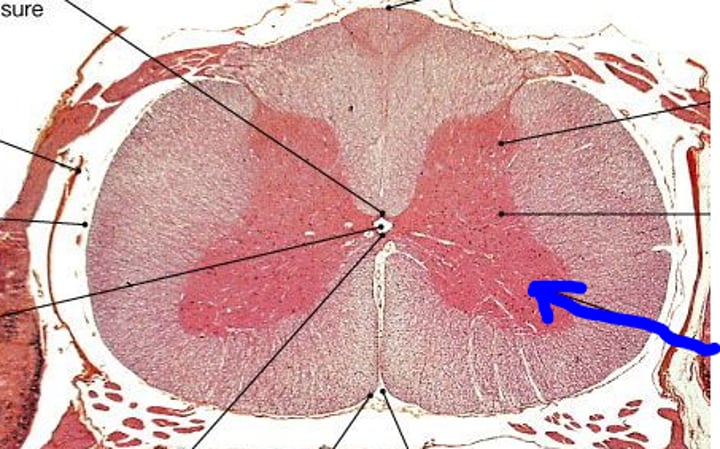

Spinal Cord Slide - anterior gray horn

Spinal Cord Slide - posterior gray horn

Spinal Cord Slide - anterior white column

Spinal Cord Slide - lateral white column

Spinal Cord Slide - posterior white column

Spinal Cord Slide - ventral root

Spinal Cord Slide - motor neurons

Spinal Cord Slide - dorsal root

Spinal Cord Slide - dorsal root ganglion

Spinal Cord Slide - unipolar neurons

Spinal Cord Slide - pia mater

Spinal Cord Slide - dura mater

Spinal Cord Slide - anterior median fissure

Spinal Cord Slide - posterior median sulcus